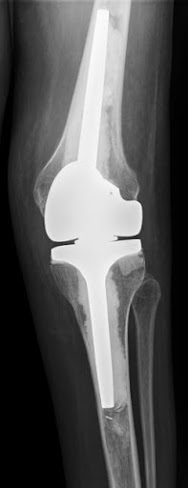

CT and Xray taken 19 years later with no symptoms. shows predictable superior wear with no periprosthetic lysis. the older standard polyethylene and 22.5 modular head in a very active gentleman